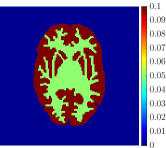

The 3D Hoffman brain phantom is composed of 250 slices, covering the entire head, consisting in black/white images of size . We reduced the image size to to resemble typical PET acquisitions, preserving the shape and features of the original phantom. For sake of simplicity, we selected a middle slice including eight anatomical structures that can be subdivided into the four homogeneous functional regions in Figure 2(a): grey matter (region 1), white matter (region 2), basal ganglia (region 3), and thalamus (region 4). Then, for each region, we assigned a ground-truth set of rate constants of the two-compartment model for FDG kinetics (described in Section 2) and a specific blood volume fraction . The numerical values of such parameters, as reported in Table 1, have been chosen in order to reproduce a realistic framework for the FDG uptake of a human brain [20, 21, 44, 45]. The ground-truth parametric images are shown in Figure 3.

The dynamic PET data were generated by solving the compartmental forward problem for each pixel of the processed Hoffman brain image. In particular, the two-compartment concentrations were evaluated by means of the integral equation (3) with the ground truth values of the compartmental parameters and the simulated IF, at 28 time frames (6 10 sec, 3 20 sec, 3 30 sec, 4 60 sec, 3 150 sec, 9 300 sec) with a time sampling typical of standard PET experiments, for a total time interval of 60 minutes. Then, the measurement equation (4) was computed to create the time concentration curves characteristic for each brain region (Figure 2(c)). The last frame of the obtained dynamic PET images is reported in Figure 2(b).